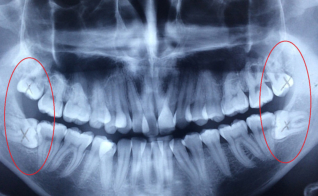

Ortodoncia reparadora

Muelas del juicio (tercer molar) con posición anómala